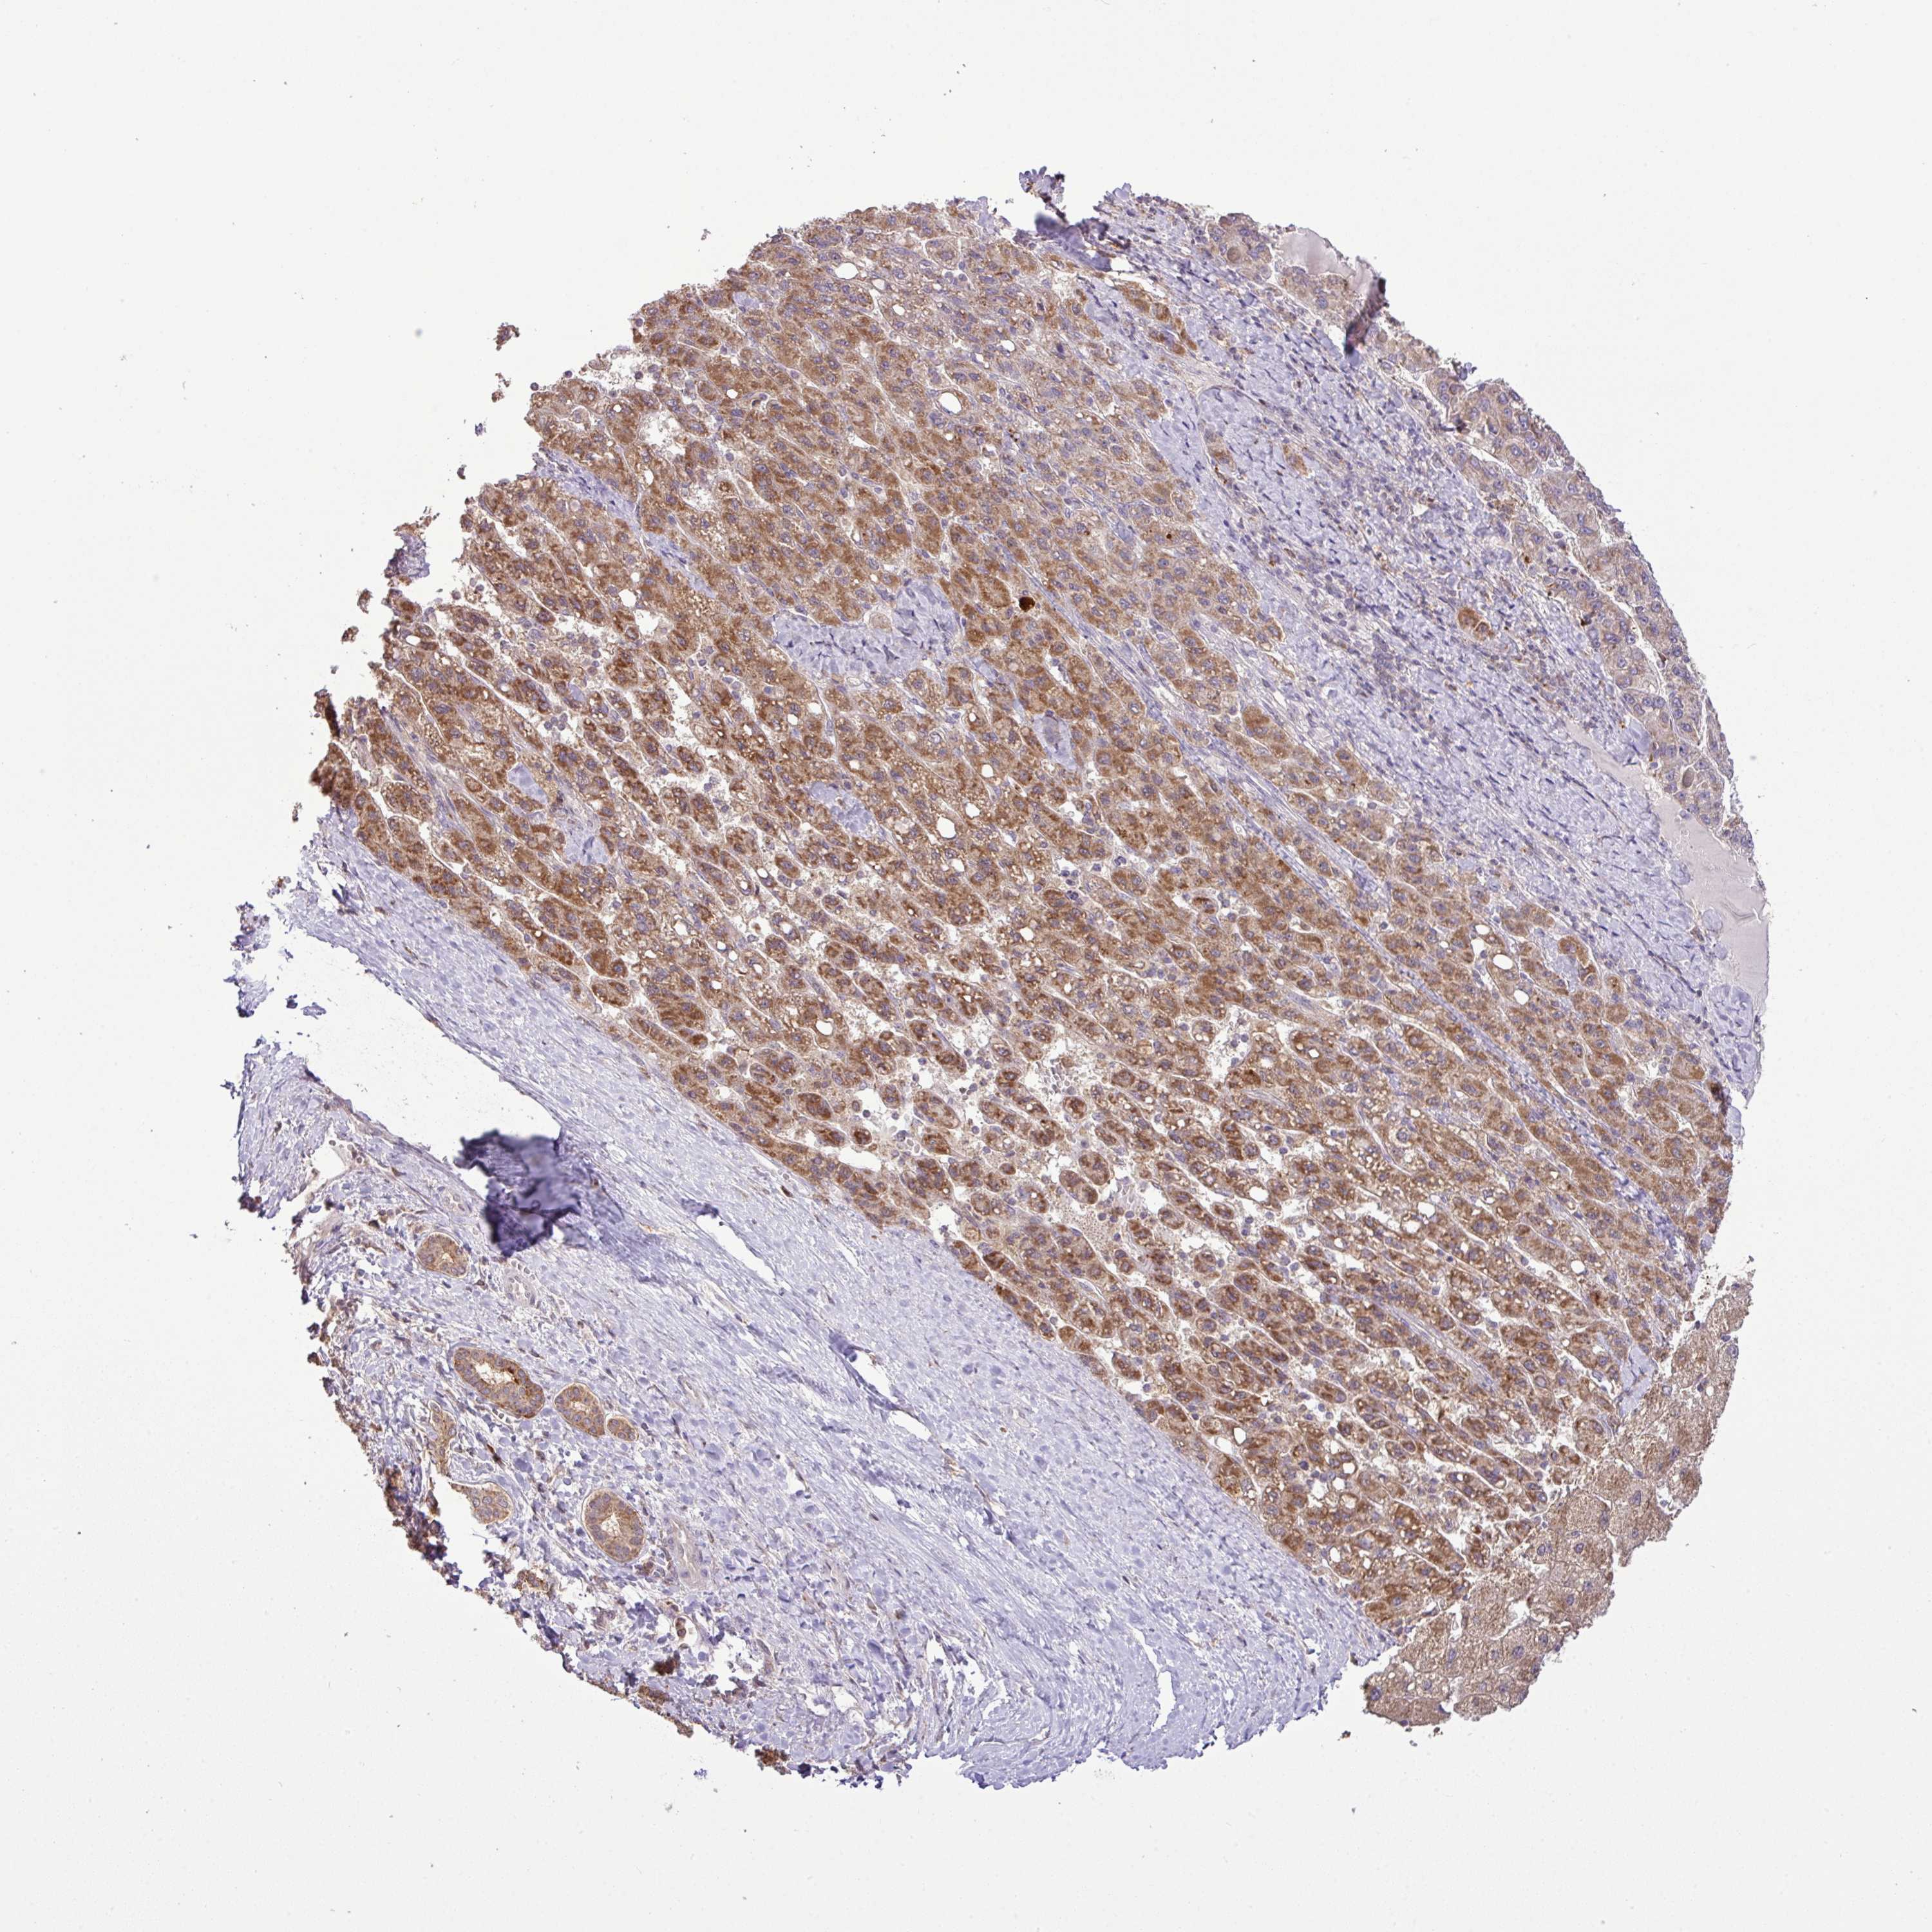

LIVER CANCER - Protein expressioni

A mouse-over function shows sample information and annotation data. Click on an image to view it in a full screen mode. Samples can be filtered based on level of antibody staining by selecting one or several of the following categories: high, medium, low and not detected. The assay and annotation is described here.

Note that samples used for immunohistochemistry by the Human Protein Atlas do not correspond to samples in the TCGA dataset.

Antibody stainingi

Antibody staining in the annotated cell types in the current human tissue is reported as not detected, low, medium, or high, based on conventional immunohistochemistry profiling in selected tissues. This score is based on the combination of the staining intensity and fraction of stained cells.

Each image is clickable and will lead to virtual microscopy that enables deeper exploration of all samples and also displays staining intensity scores, fraction scores and subcellular localization as well as patient and tissue information for each sample.

Antibody HPA041120

Staining

High

Medium

Low

Not detected

Intensity

Strong

Moderate

Weak

Negative

Quantity

>75%

75%-25%

<25%

None

Location

Nuclear

Cytoplasmic/membranous

Cytoplasmic/membranous,nuclear

Cholangiocarcinoma

Carcinoma, Hepatocellular, NOS